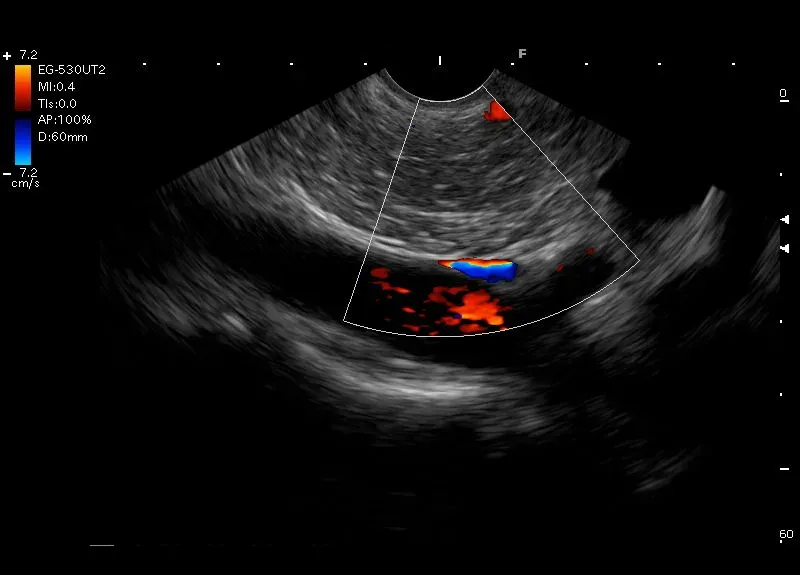

Drobne, linijne, hiperechogeniczne odbicia, bez cienia akustycznego, widoczne w trzonie trzustki - zmiany mogące odpowiadać zwłóknieniom w trzustce